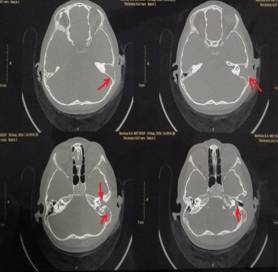

該患兒既往無中耳炎及耳流膿病史,僅表現(xiàn)為1個(gè)月前耳后稍有紅腫、疼痛,在當(dāng)?shù)蒯t(yī)院曾被診斷為“蚊蟲咬傷”所致,家長也未引起足夠的重視。近半月來,患兒耳后紅腫疼痛加重,遂到我市某三甲醫(yī)院就診,行高分辨率中耳乳突CT,發(fā)現(xiàn)側(cè)顱底、中耳乳突腔巨大新生物占位,乳突骨皮質(zhì)破壞吸收,并可疑耳后骨膜下膿腫形成。病情若進(jìn)一步發(fā)展,膽脂瘤破壞顱底骨質(zhì),將極有可能并發(fā)腦膜炎、腦膿腫,甚至出現(xiàn)敗血癥、腦疝等,危及生命。

1.術(shù)前耳后紅腫 2.術(shù)前CT1